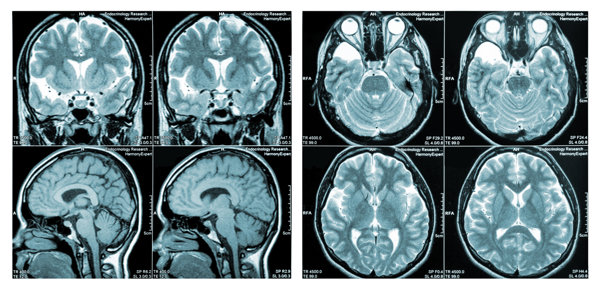

2026年3月28日自闭症做核磁共振可以检查出大脑结构和功能上的异常。

自闭症是一种神经发育障碍,通过核磁共振成像(MRI)可以观察到大脑结构和功能上的差异,帮助医生了解自闭症患者的脑部情况,为治疗提供依据。

自闭症患者的大脑在结构和功能上可能存在异常,通过核磁共振成像可以观察到这些差异。MRI可以提供大脑的详细图像,帮助医生识别大脑中可能与自闭症相关的特定区域的异常,如白质、灰质、脑室大小等。需要注意的是,MRI结果并不能直接确诊自闭症,它只是辅助诊断的一部分。自闭症的确诊需要综合考虑患者的临床表现、行为特征和发育情况。